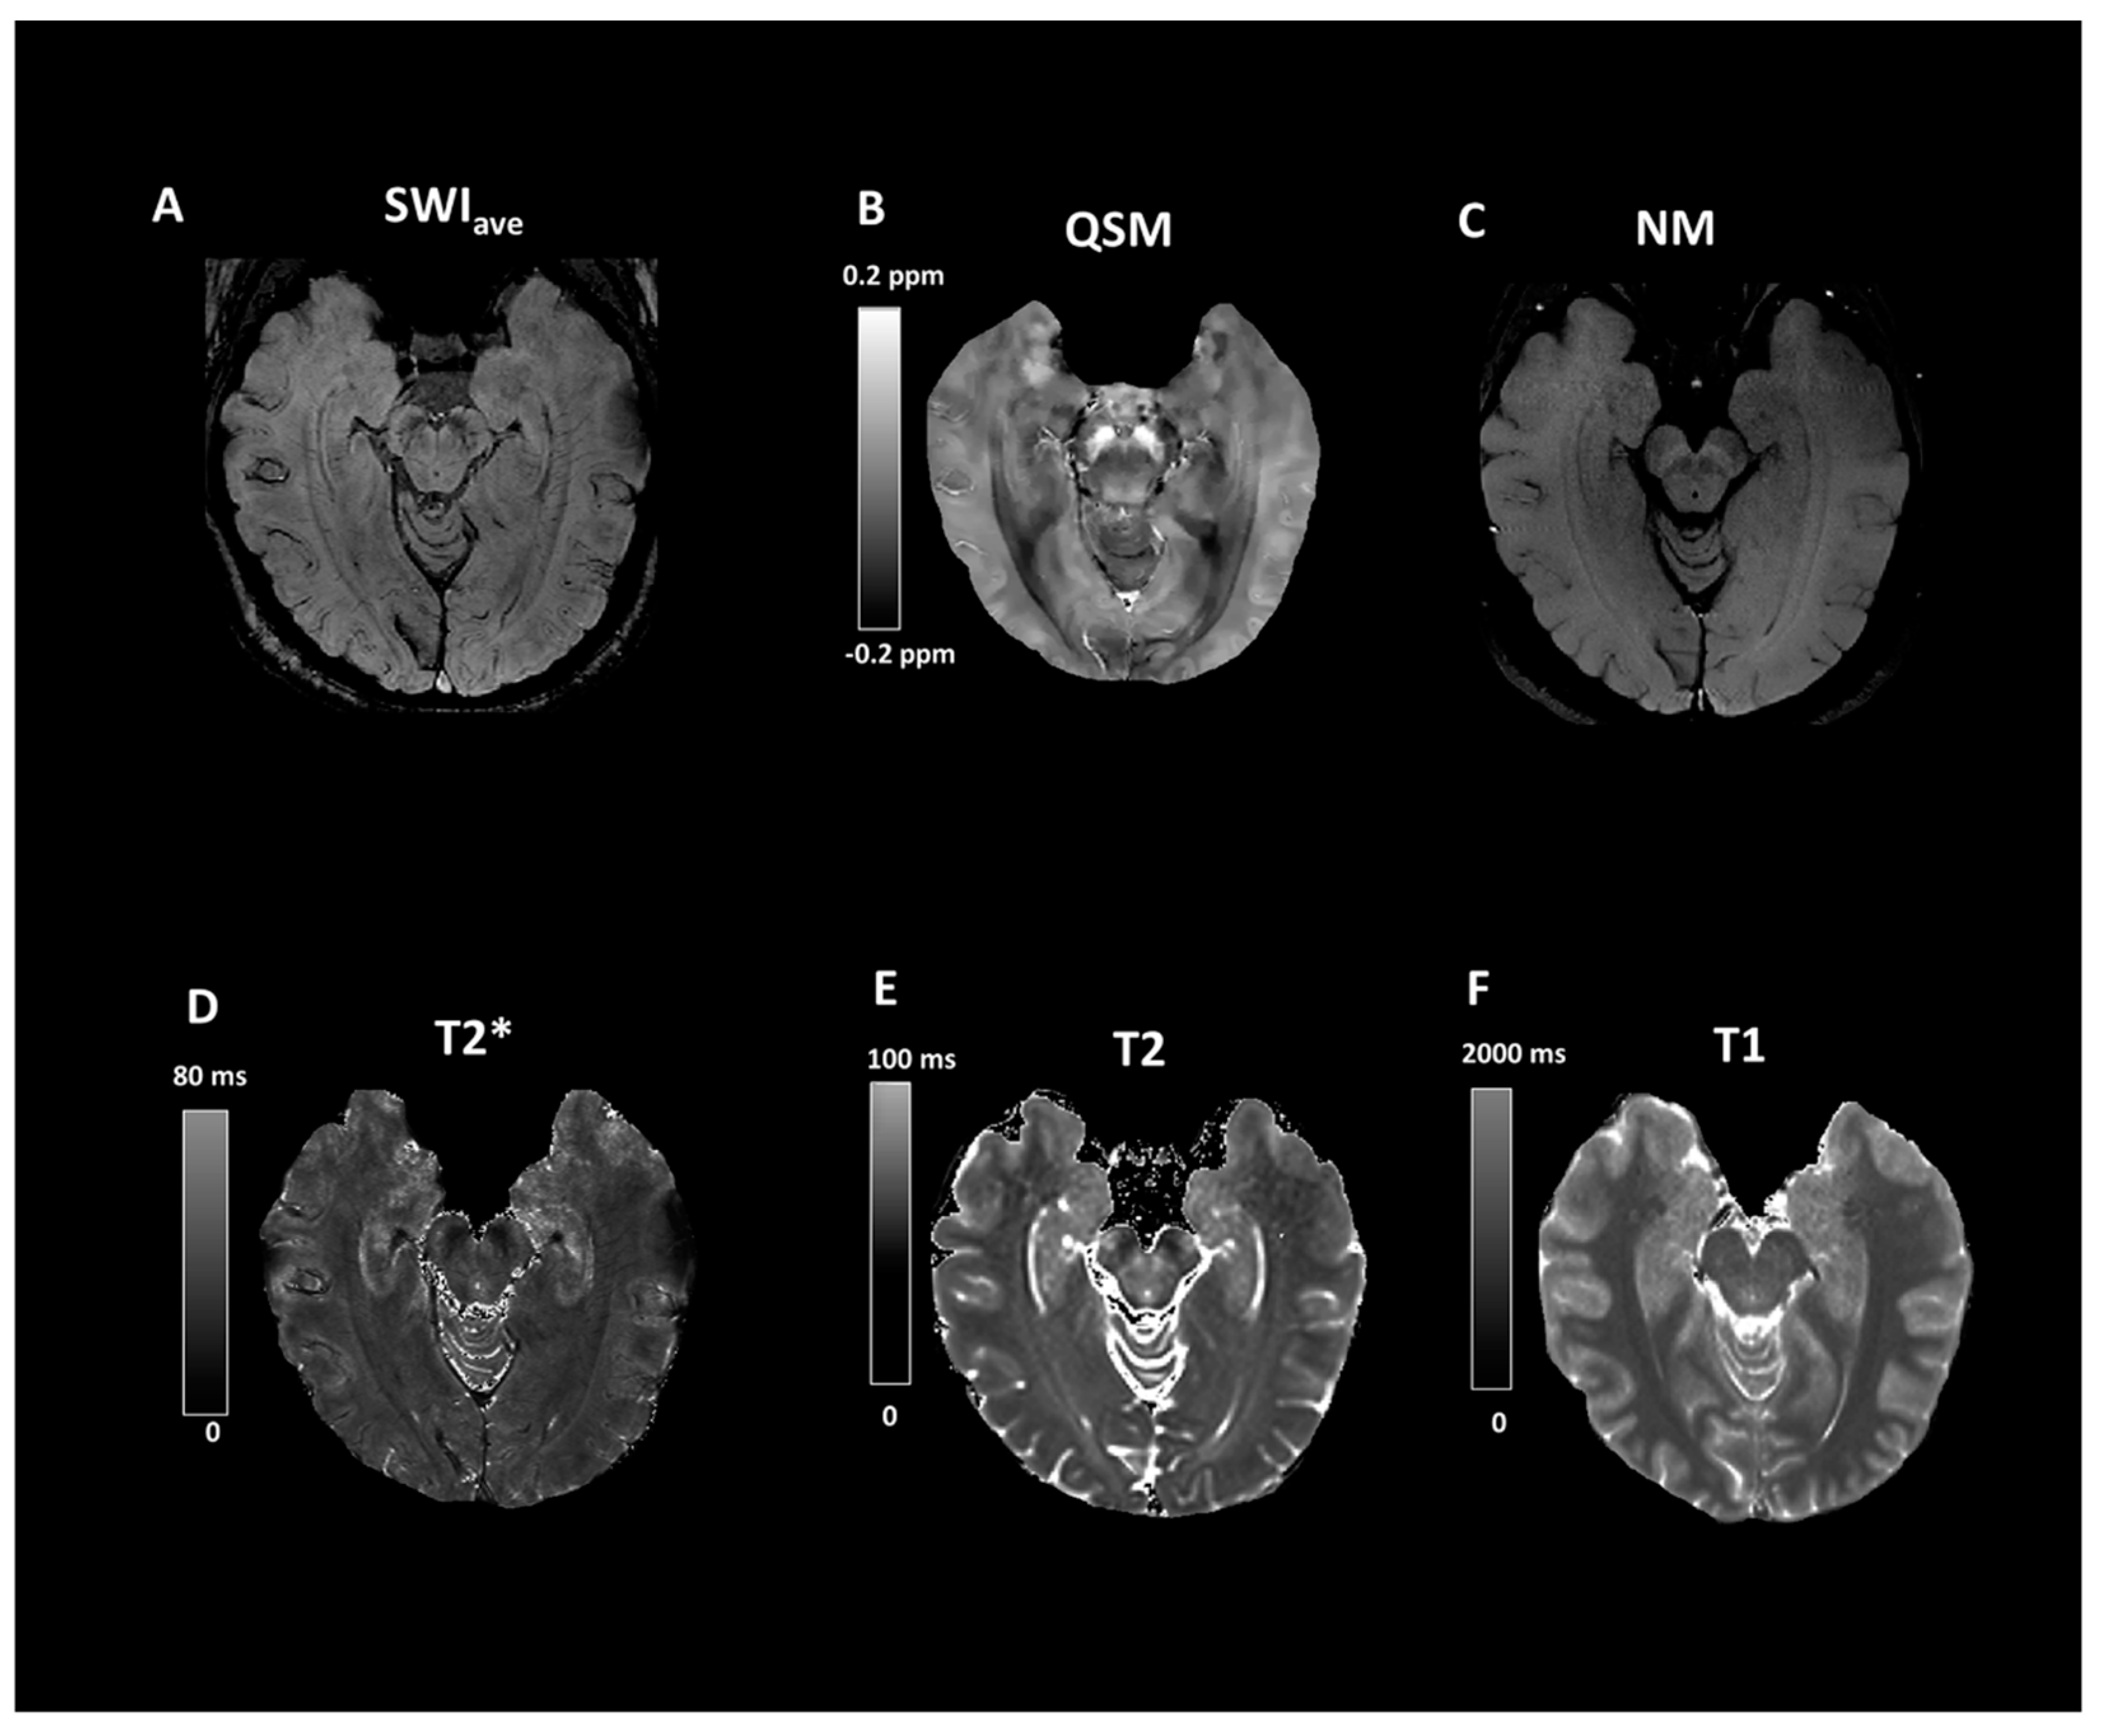

2.2. Imaging Protocols

2.3. Imaging Data Analyses

3. Results

4. Discussion